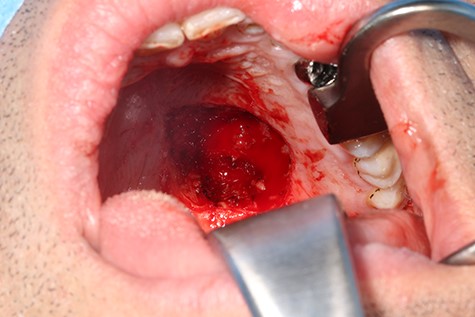

A 37-year-old patient with a recurrent, histologically confirmed steatocystoma of the palate was referred to our clinic. The patient’s medical history had already included two local removals of the tumor. Clinically, in the transition from hard to the soft palate, an asymptomatic, about 1 cm large, round, circumscribed and soft lesion was seen (Fig. 1). Magnetic resonance imaging was performed for further diagnosis and for assessment of spread and tissue infiltration of the finding. Here, a submucosal, 8 × 10 × 8 mm large tumor of delimited growth could be verified. It was T1 hypertense, T2 inhomogeneous partly hypointense, partly isointense with a significant signal drop in the T2 fat saturation (Fig. 2). There was no evidence of bony infiltration. The lesion was resected with a safety margin of 1–2 mm protecting the nerve and the greater palatine artery up to the palatal bone (Figs 3 and 4). As a secondary granulation of the defect was intended, the wound was first treated with a cellulose tamponade and tranexamic acid gel to prevent bleeding. An acrylic splint was then incorporated as a pressure bandage and wound protection (Fig. 5). The histopathological examination of the removed specimen showed a soft and glandular tissue covered with squamous epithelium with manifestations of a cystic, regressively changed epithelial lesion, which was compatible with the clinically known steatocystoma (Fig. 6). Follow-up examinations at 3-month intervals showed a good wound healing with complete restitution without evidence of recurrence after 1.5 years.

Clinical appearance of the tumor in the transition from hard to the soft palate on the left side of the mouth